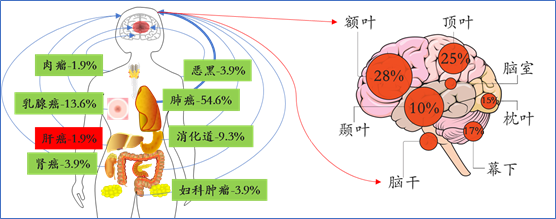

肝癌及脑转移发病率:脑转移瘤以肺癌来源为最多,占比可达40%~60%,其次为乳腺癌,其它来源有胃肠道肿瘤、肾癌、妇科肿瘤、肝癌等;其中,肝癌脑转移占所有脑转移瘤的1-2%左右;另外,肝癌患者发生脑转移概率大约为0.2%~2.2%。

肝癌脑转移位置分布及特征:可发生于脑的任何部位,最常见于幕上大脑半球,尤其是大脑中动脉供血区的灰白质交界处,约30%-40%为单发,60%-70%为多发;肝癌脑转移易合并肿瘤出血,发生率为39.5%-66.7%。

复旦肿瘤神经外科脑转移瘤数据